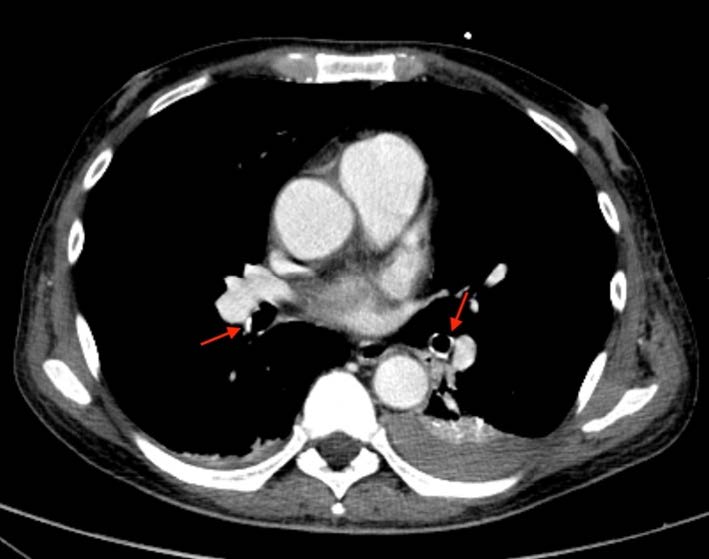

A 57-year-old man with long-lasting chronic kidney disease due to post-streptococcal glomerulonephritis was referred to our nephrology clinic to perform a second renal transplantation. The patient had a 28-year history of hemodialysis treatment and a first kidney transplant failure. Impaired renal function with normal calcemia, slightly elevated phosphorus, and hyperparathyroidism were observed through laboratory tests. During the previous 3 months, he had a history of non-productive cough with persisting dyspnea. His physical examination was unremarkable. The chest radiograph (Fig.1) revealed numerous small nodular opacities with patchy areas of parenchymal opacification. The nodules were predominant in the upper lung zone and calcification of the nodules was evident. Computed tomography (CT) of the chest showed multiple ground-glass opacities associated with poorly defined centrilobular nodules with ground-glass attenuation and coarse areas of calcification (Fig. 2). There was a symmetrical distribution involving both upper lung lobes and also bronchial calcifications (Fig. 3). There were no visible signs of pleural effusion, pulmonary fibrosis, or lymphadenopathy. Based on these findings and in this setting of end-stage renal disease, the diagnosis of metastatic pulmonary calcification (MPC) was made. Attempt to normalize the patient’s calcium and phosphate biochemistry has been the mainstay of therapy. Following treatment, the patient’s imaging abnormalities have been stable, and he is now waiting for a new transplant match.

Due to the high levels of serum calcium and phosphate, calcium deposits can occur in any organ of the body, with a predilection to sites disposed to alkalinity, such as the lungs, kidney, and stomach. In the lungs, calcium salt deposits are usually located in the alveolar epithelial basement membranes, with an affinity for elastic tissue. It can also appear in the walls of the bronchioles and pulmonary vessels, explaining the interstitial and centrilobular location of the findings. Sporadically, calcifications can also be found in the large airways.3,10 In moderate situations, there is calcium deposits in the alveolar epithelial basement be found.11 Also, a diffuse interstitial process or confluent calcified nodules are other possible forms of presentation. Imaging with CT is a sensitive diagnostic tool in pulmonary calcification diagnosis and much more accurate on its detection. Three different patterns of MPC have been described in literature: - multiple millimetric diffuse calcified nodules, which can be distributed through the whole lung or have a predilection for the apices; - diffuse or patchy areas of ground-glass opacity/consolidation; - confluent high-attenuation parenchymal consolidation with a lobar distribution, mimicking lobar pneumonia.9 The most common parenchymal finding on chest CT is numerous ill- defined fluffy centrilobular nodules that may contain foci of calcification. Well-defined areas of dense consolidation can be seen in cases of severe interstitial calcification. These findings are the consequence of calcium deposition in the alveolar walls around the terminal bronchioles. In addition to parenchymal pulmonary abnormalities, calcification of the chest wall vessels, bronchial walls and myocardium are also a possible findings.13 In our case, CT scan showed some typical MPC findings such as multiple bilateral centrilobular ground-glass opacities and areas of consolidation distributed throughout the upper lung zones, and bronchial calcifications. The higher ventilation-perfusion ratio in the upper lobes leads to a lower end capillary PCO2 and a consequent higher pH. This physiological phenomenon is the main reason why calcium deposits are mainly located in the upper lung area instead of the lung bases.15 Innovating imaging techniques such as spectral-detector computed tomography (SDCT) may be highly useful to clarify and confirm the suspicion of calcified nodules or ground-glass opacities present in conditions as MPC. A recently published case showed that when using a calcium-suppressed images in SDCT, the ground-glass opacities and parenchymal calcifications “vanish” in opposite to other pulmonary infiltrations such as pneumonia and pulmonary edema, which would be unchanged by calcium suppression.16 This is possible due to the additional spectral information used in this technique which allows the subtraction of calcium from the reconstructed images, once materials have attenuation profiles at different energy levels.17